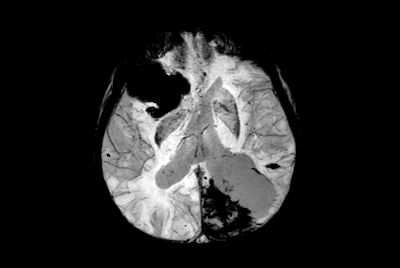

Pediatric brain with AVM